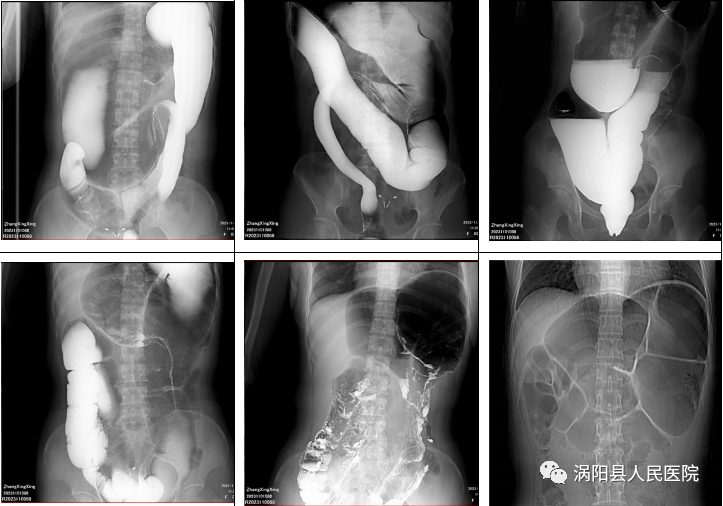

图中白色物质为钡剂

右侧为病变肠道)